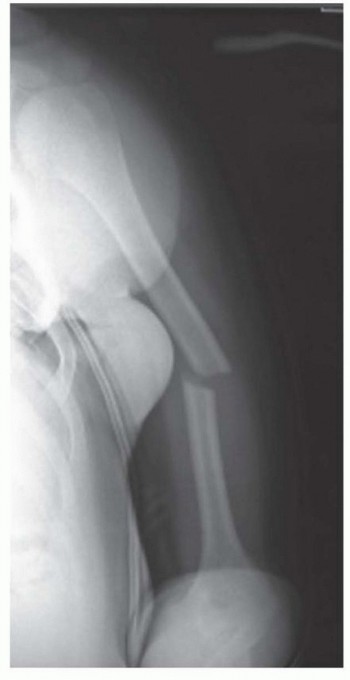

Chapter 17 Plate Fixation of Humeral Shaft Fractures Matthew J. Garberina Charles L. Getz DEFINITION Humeral …